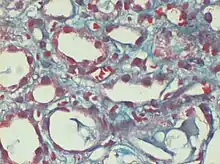

Trichrome de Gomori

Capillaires péritubulaires dilatés remplis de globules rouges falciformes, coloration originale au trichrome de Gomori, × 400.